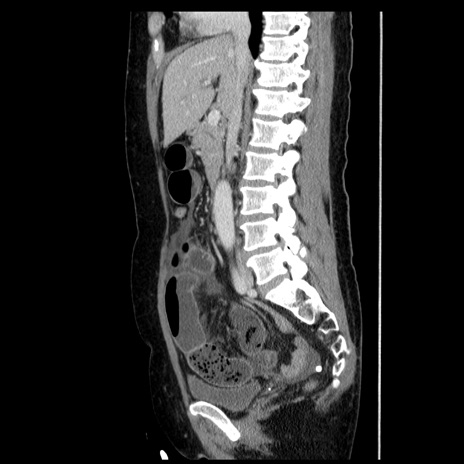

症例6(矢状断像)